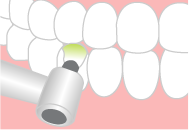

PMTCとは、専門的なクリーニングです。

蓄積してしまいがちな着色汚れや歯石や歯垢、細菌(バイオフィルム)を取り除き、むし歯や歯周病を防ぎます。

| 1.歯石・歯垢の除去 |  |

専用の器具で、徹底的に歯石・歯垢を除去していきます。 |

| 2.研磨 |  |

専用のブラシとフッ化物入りのペーストを用いて、歯の着色を取り除き、1本1本丁寧に磨いていきます。 |

| 3.フッ素塗布 |  |

むし歯を予防する効果のあるフッ素を、歯と歯の間や表面に塗っていき、むし歯になりにくい歯にしていきます。 |

当院では、歯科衛生士が一回1時間をかけて、しっかりと処置をおこなっております。